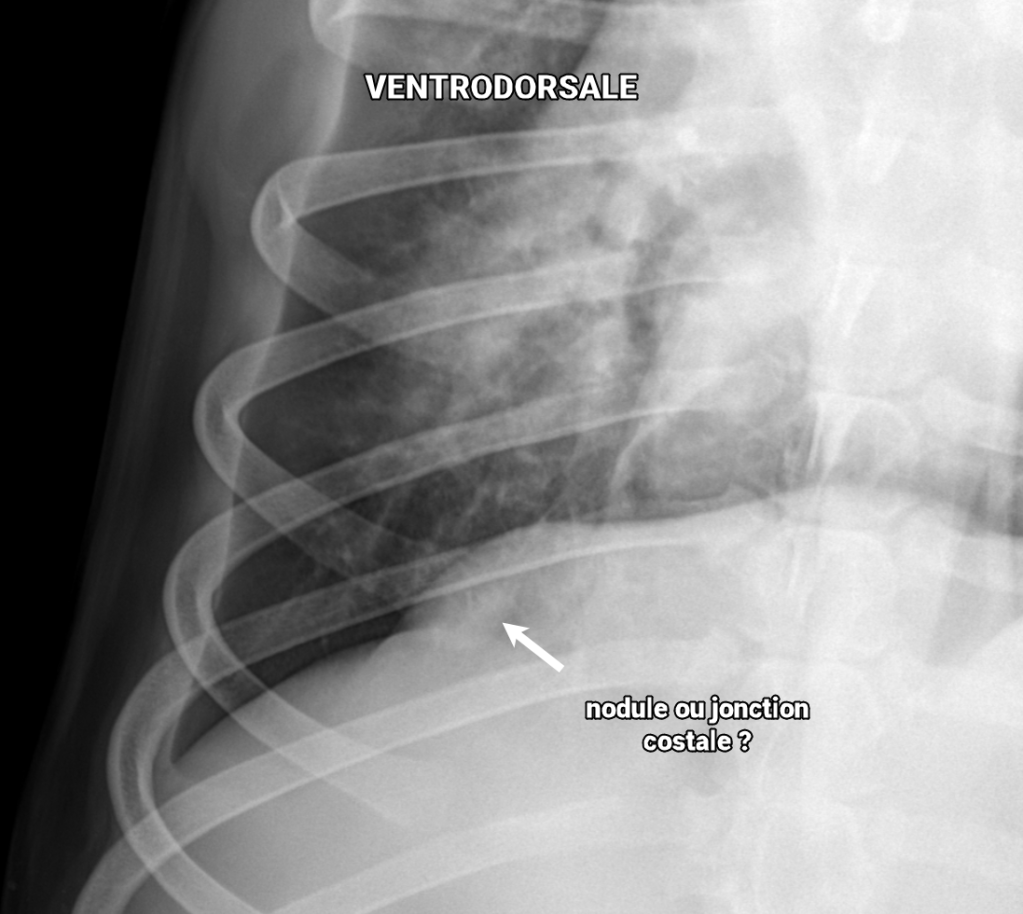

Ce concept s’applique aussi à la détection de nodule ou de masse pulmonaire caudodorsale. À l’inverse, les structures situées dans les poumons ventraux (incluant le lobe accessoire) sont mieux visibles sur une VD comme ces portions sont alors mieux ventilées.

Ce chien boxer croisé de 12 ans mâle castré avait été présenté pour toux, vomissements et bruits respiratoires augmentés à l’examen. En plus de la pathologie alvéolaire ventrale signalant une bronchopneumonie, un nodule pulmonaire caudo-dorsal était suspecté sur les vues latérales (flèches jaunes), mais n’était pas bien visible sur la VD soumise à ce moment.

Lors du suivi radiographique de la bronchopneumonie, une DV a été effectuée et a permis de confirmer le nodule pulmonaire au lobe caudal droit.